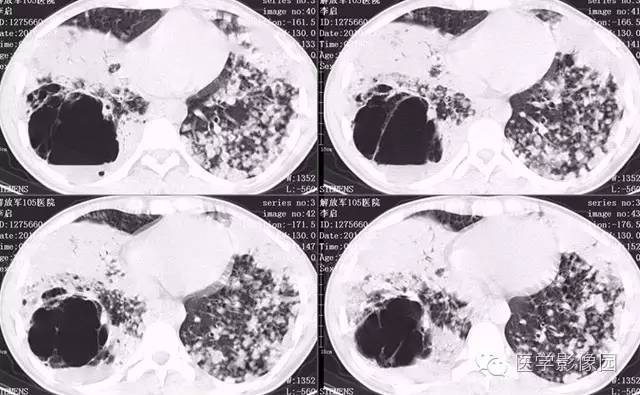

病理结果:弥漫性肺泡细胞癌

弥漫性肺泡癌的主要临床及CT表现:临床表现无明显特征, 随着病情的进展, 咳嗽、 咳白痰、 进行性气促。CT表现 为病变分布有两种情况:病变累及一个肺段或肺叶;病变广泛分布于两肺。可归纳为5个特征性征象:蜂房征;支气管充气征;磨玻璃征;血管造影征;两肺弥漫分布的斑片状与结节影。